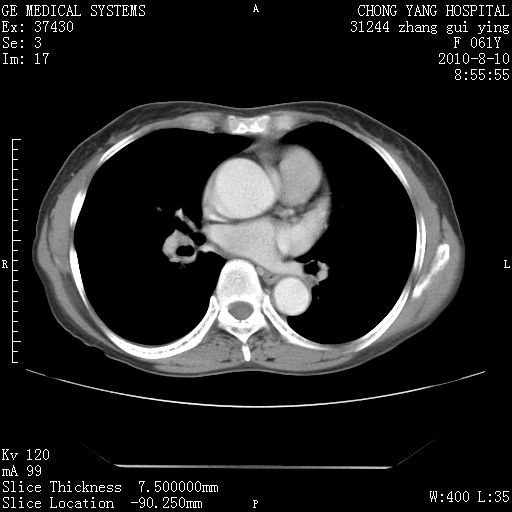

标题: CT28314:F61Y胸部增强,发热咳嗽一周入院,后面的为一周前平 [打印本页]

标题: CT28314:F61Y胸部增强,发热咳嗽一周入院,后面的为一周前平

1、支持考虑右侧中央型肺癌伴右肺中叶节段性不张及下叶支气管黏液痰栓    2、左肺上叶舌段感染。

支持3楼意见,还要考虑:纵隔及肺门淋巴结转移、右侧少量胸腔积液。

确切的说:1:右肺下叶中心型肺癌侵及中叶支气管并中叶不张,纵膈淋巴结转移。2:左肺舌叶炎症。3:右侧胸腔少量积液

块影平扫32hu,动静脉期62-70hu.